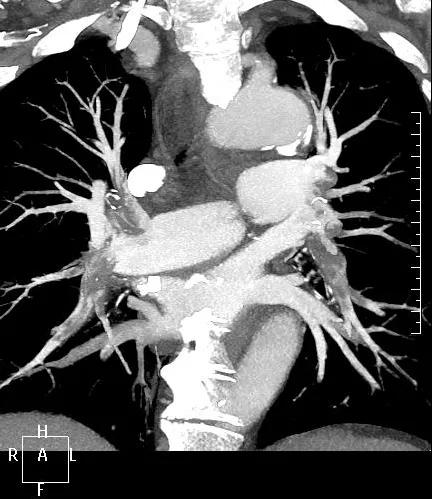

近日,一名港胞翁阿姨在我市突發(fā)急性肺栓塞,生命垂危。市二院在接到120出車指令后,迅速響應(yīng),患者入院后開通綠色通道,經(jīng)急診科、心內(nèi)科、介入科、重癥醫(yī)學(xué)科等多學(xué)科專家開展聯(lián)合會診,并于當(dāng)晚9點(diǎn)行“下腔靜脈、肺動脈造影+導(dǎo)管溶栓+濾器植入術(shù)”,患者終于轉(zhuǎn)危為安,經(jīng)后續(xù)治療與精心護(hù)理,病情逐漸穩(wěn)定,現(xiàn)已轉(zhuǎn)入普通病房。